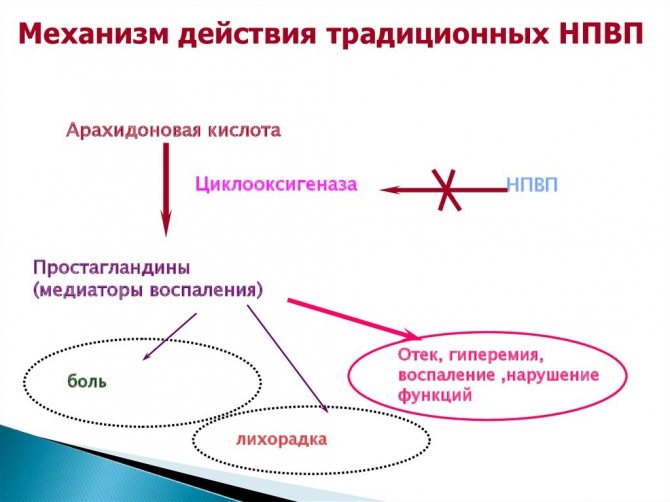

Лечение выпячивания осуществляется двумя методами: консервативным и оперативным. Традиционная терапия включает в себя прием противовоспалительных нестероидных медикаментов. К ним относят, например, такие средства, как «Напроксен» или «Ибупрофен». Также в комплекс консервативных мероприятий входит физиотерапия. Она направлена на высвобождение защемленных корешков и стабилизацию позвоночника. Существуют специальные комплексы упражнений, рекомендуемые пациентам. Сначала это могут быть приседания и медленные наклоны. При обострении рекомендован 2-дневный постельный режим. Дольше лежать не следует, поскольку восстановиться будет труднее. В случае отсутствия результата после консервативных мероприятий применяют оперативный метод. Хирургическое вмешательство, как правило, позволяет быстро и на длительный период избавиться от патологии. Однако при этом возможен рецидив.

Консервативное лечение должно быть комплексным. Оно направлено на уменьшение болевого синдрома, снижение мышечного спазма, улучшение трофики тканей в области грыжи, купирование воспаления. Лечение запускает процесс регенерации соединительной ткани, восстановление нормального положения диска.

В первую очередь используют нестероидные противовоспалительные средства, которые уменьшают боль и снимают отек. Это могут быть Диклофенак, Нимесулид, Кетанов.